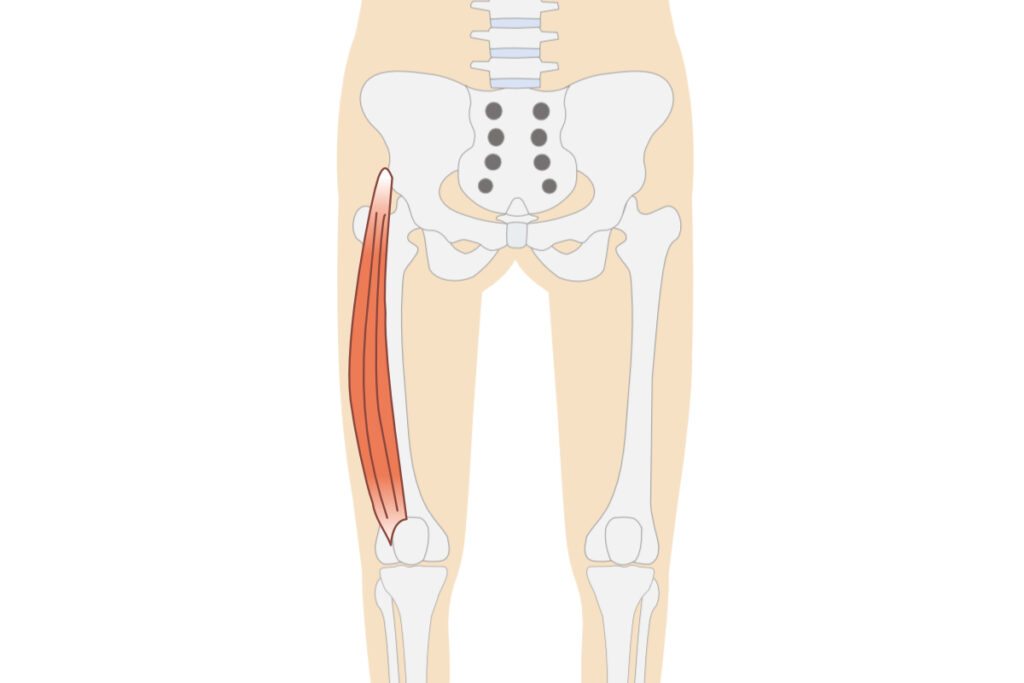

膝の痛みの原因になりやすい筋肉の例

外側広筋

膝の痛みの原因になりやすい部位を中心に刺激

外側広筋

刺激するポイントは個人差があり、その日の体調によっても変化します(イラストは参考図)